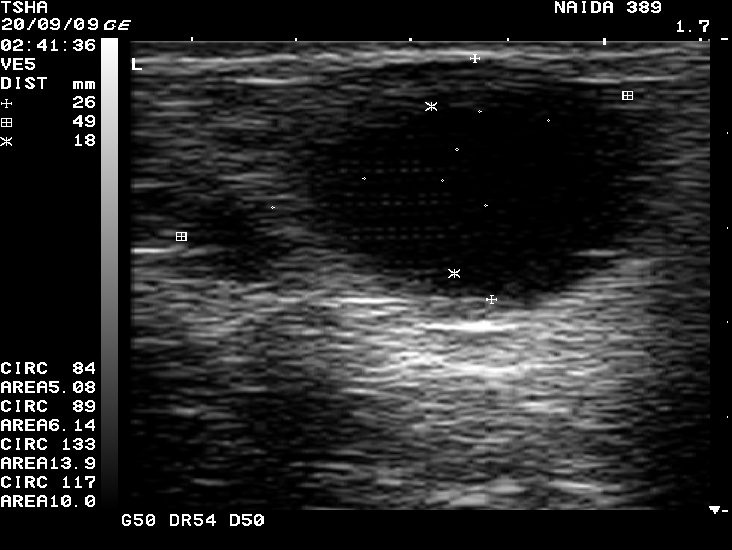

Рис.4. Спонтанное восстановление половой функции у коровы Найда 389 с крупными фолликулярными кистами в правом и левом яичниках. На 9 день наблюдения корова пришла в охоту и плодотворно осеменена. В правом яичнике отметили образование крупного желтого тела диаметром 38 мм. Регрессия кист, особенно со стороны правого яичника, происходила медленно. К 21 дню наблюдения ее диаметр уменьшился в диаметре всего на 6 мм (с 48 до 42 мм)